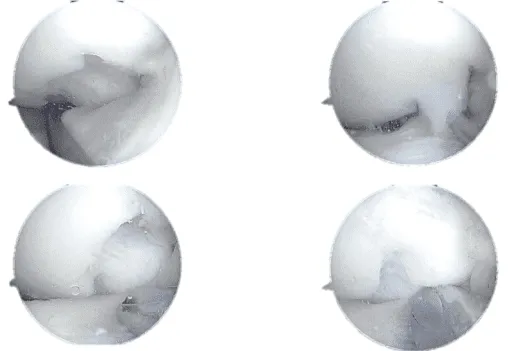

Se encontró que el menisco lateral se extruía hacia la región intercondilar. Se introdujo la sonda y se examinó el desgarro que se encontraba alrededor de la sustancia media con deshilachado en los bordes meniscales.

No se encontró que el desgarro fuera reparable. El menisco desgarrado fue retirado con puñetazos y una afeitadora. El cuerno anterior tenía un quiste meniscal, que se descomprimía usando la afeitadora.

El desbridamiento extenso del menisco llevó a la extirpación del 60% al 70% del menisco, con la retención del borde periférico, parte del cuerno anterior y del cuerpo anterior y posterior.

El daño condral se encontró en la parte posterolateral del cóndilo femoral lateral, que medía más de 20 mm x 5 mm. Era daño condral de grado 3 a 4 de OA. Se realizó la condroplastia, el daño fue suficiente para necesitar un procedimiento reconstructivo secundario para el cartílago.

Desgarro artroscópico del menisco lateral posterior